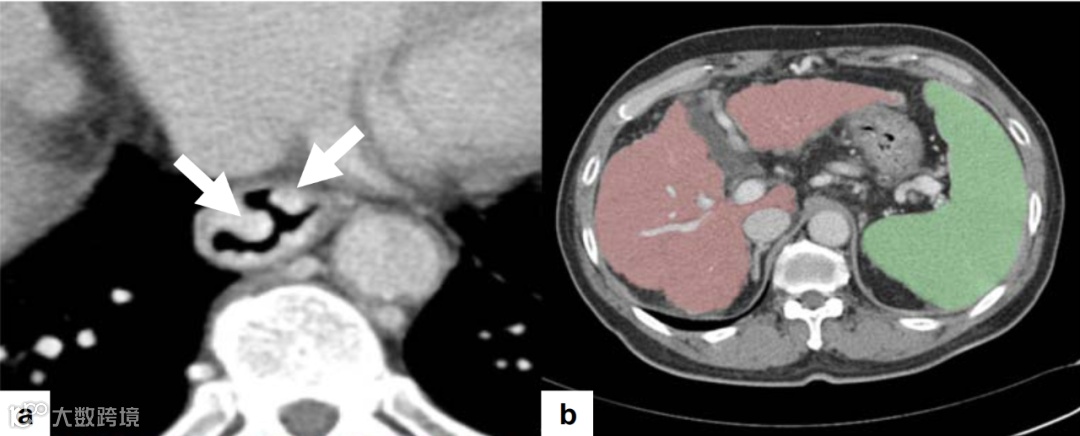

深度学习算法可以在CT图像上自动测量肝脏和脾脏的体积。近日,来自韩国蔚山大学医学院的Chul-Min Lee等人建立了一个结合肝脾体积和临床因素的指标,以诊断乙型肝炎(乙肝)代偿期肝硬化患者中的高出血风险静脉曲张。

该研究回顾性纳入了419例乙肝肝硬化患者,这些患者分别于2007年至2008年(训练队列,n=239)和2009年至2010年(验证队列,n=180)接受内镜和CT检查。使用深度学习算法在CT图像上测量肝脏和脾脏体积。在训练队列中采用多因素逻辑回归分析建立了一个诊断经内窥镜确认的高出血风险静脉曲张的指标。按指标值对患者进行分层,评估了5年内累积的静脉曲张出血风险。

研究者根据训练队列的数据建立了脾脏体积与血小板比率的指标。在验证队列中,平衡临界指数值(>3.78)诊断高出血风险静脉曲张的敏感性为69.4%和特异性为78.5%,而高敏感性临界指数值(>1.63)能检测到所有高出血风险静脉曲张。该指数将所有患者分为低风险组(指数值≤1.63;n=118)、中等组(n=162)和高风险组(指数值>3.78;n=139);静脉曲张出血5年累积发生率分别为0%、1.0%和12.0%(P<0.001)。

因此,通过基于深度学习算法的CT分析获得的脾脏体积与血小板比率可用于诊断高出血风险静脉曲张和评估患者静脉曲张出血的风险。

本研究目的在于评估CT在乙肝代偿期肝硬化患者中诊断高危静脉曲张的价值。以往研究结果显示,即使CT图像上没有明显的静脉曲张表现,也不能完全排除高危静脉曲张的风险。因此该研究采用基于CT图像的深度学习方法,利用常规实验室数据和肝脏、脾脏体积数据开发了一个预测高危静脉曲张的指数。

结果显示,脾体积/血小板指数(脾脏体积与血小板比率)对高危静脉曲张的检测效果良好,可以根据该指数对患者静脉曲张出血风险进行分层。更重要的是,利用基于CT图像的深度学习方法获得的脾脏体积与血小板比率,可以识别出静脉曲张出血的可能性非常低的肝硬化代偿期患者,以避免不必要的内镜检查。

该研究团队的思维方法给医学影像及其他辅助科室的临床及科研很大启示:精确诊断疾病固然非常重要,同时还要重视排除诊断,这可以为患者减少不必要的检查和支出。该研究的亮点在于通过深度学习算法实现了脾脏体积的全自动精确测量,这表明基于深度学习的自动CT脾脏体积测量可能在临床上适用,可以在常规CT评估中添加更多诊断信息,而无需占用放射科医生或临床医生额外的时间和精力。本研究结果局限于代偿期乙肝肝硬化患者,尚不能推广到其他病因导致的代偿期肝硬化。